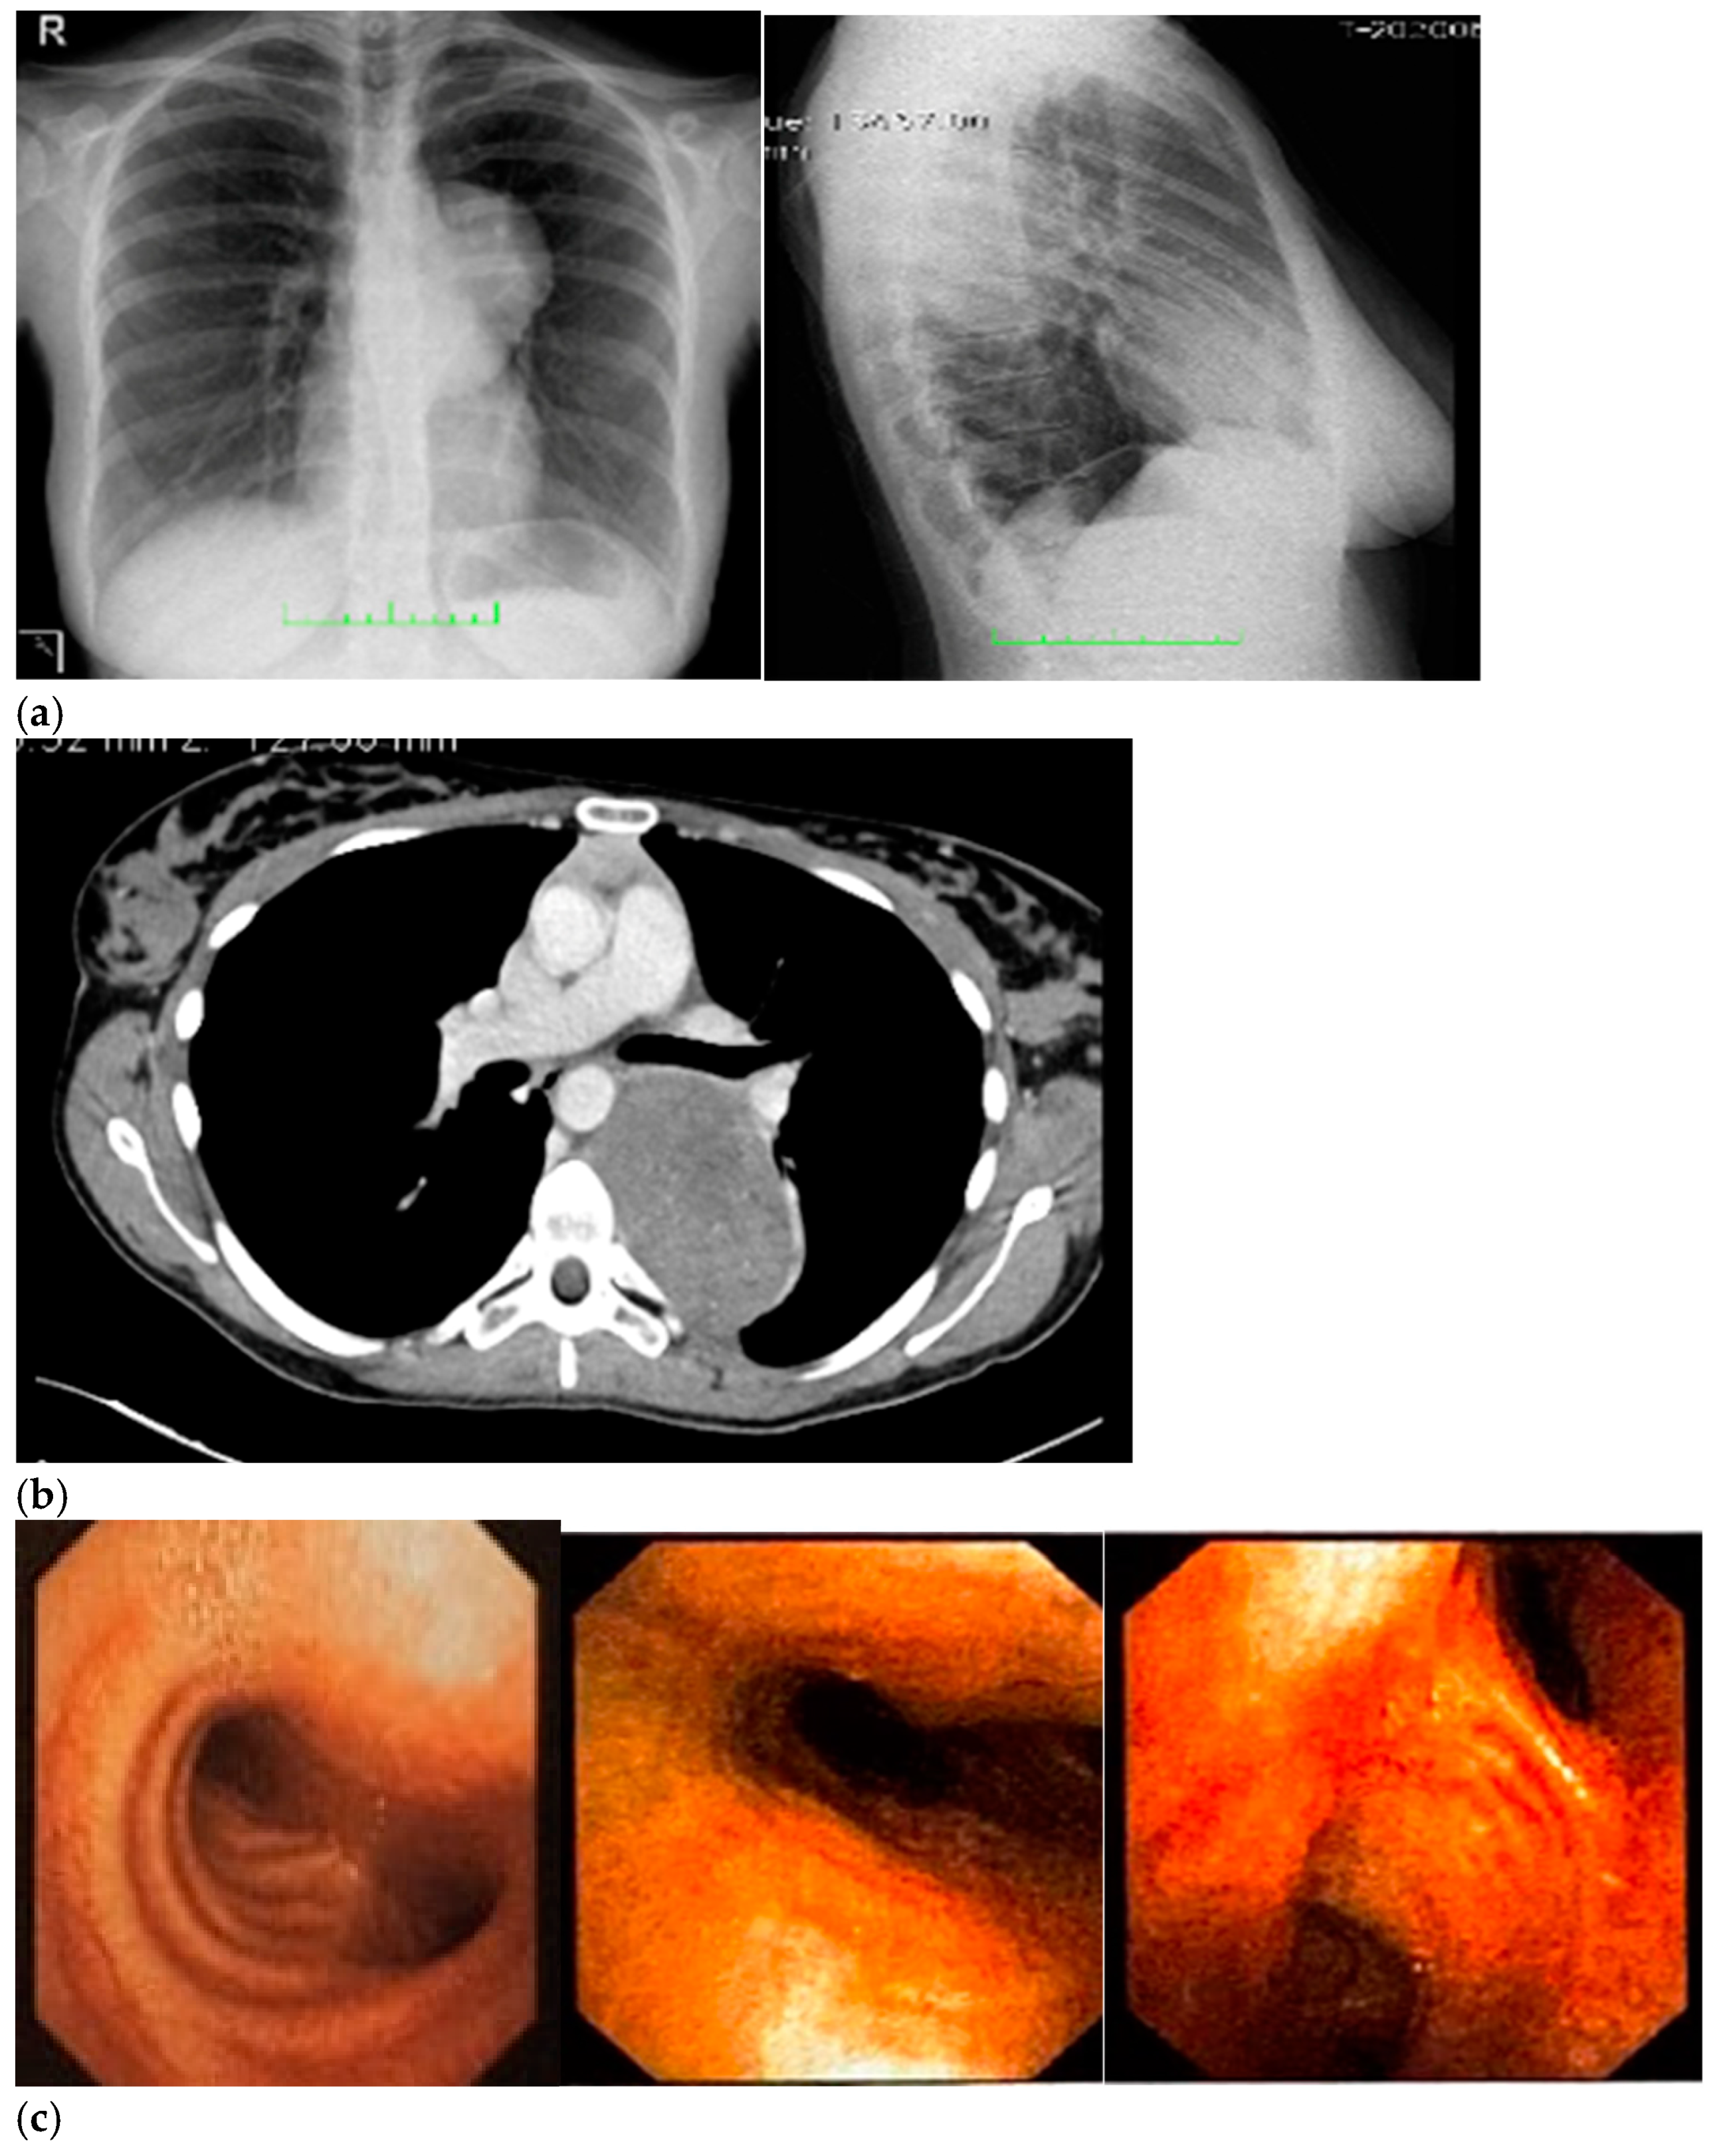

Ten days after surgery, the patient stopped taking her pain medications and was able to sleep on her left side again; afterwards, her sutures were removed, and the patient underwent an imaging check-up, which had negative results (Figure 2).

Figure 2.

(a–c) Imaging assessments for post-surgical evaluation. (a) X-rays. (NOTE: No signs of ongoing pleuropulmonary lesions, free pulmonary bases, each hilum had a normal morphology, heart and aorta within normal limits, normal mediastinum). (b) Total-body scintigraphy with metaiodobenzylguanidine. (NOTE: No longer detectable pathological activity in the left hemithorax. No other areas of significant radiopharmaceutical were observed). (c) Thorax MRI with Gadoteridol. (NOTE: Outcomes of the surgical removal of the well-known left paravertebral lesion and a thin fluid layer corresponding to the surgical cavity. Very little slightly hyperintense remaining tissue in T2-weighted images, with subtle contrast enhancement and a maximum size of about 15 mm, at T6–T6 level, on the left side of the intervertebral foramen, close to the same level costovertebral joint—in a clinical picture which required MRI monitoring with contrast medium overtime).